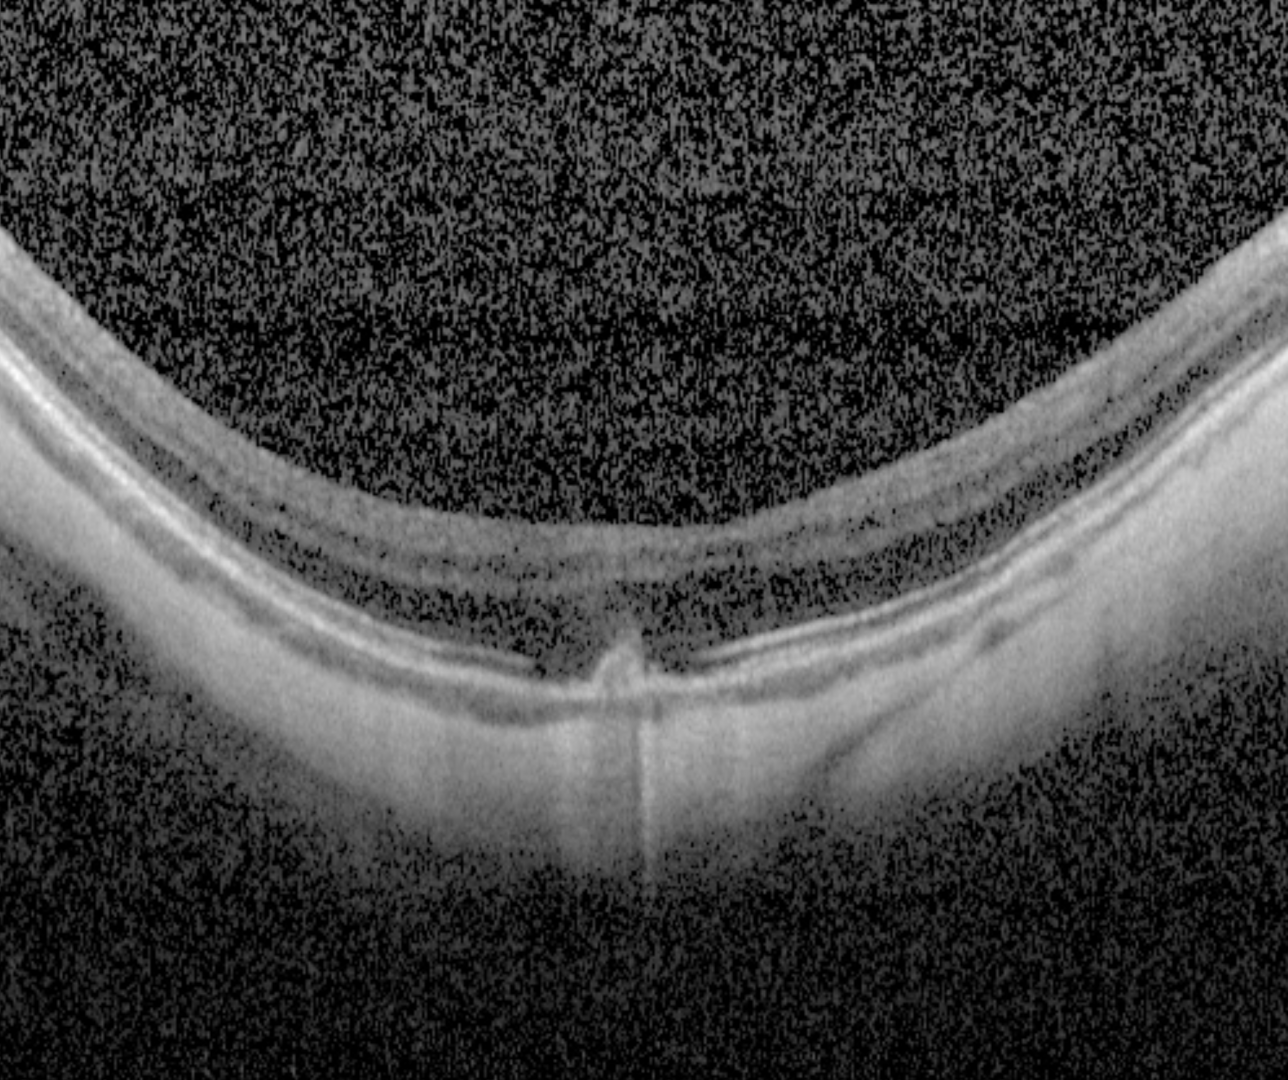

When associated with a lacquer crack, OCT shows a hypo-reflective break in the RPE-Bruch's membrane complex with a "volcanic"-like appearance. There are no signs of associated exudation present.

When associated with myopic CNV, the CNV presents on OCT as a hyper-reflective sub-retinal lesion usually with associated subretinal fluid. More information about myopic CNV is available by clicking on the tab at the bottom of this page.

A 59 year old Caucasian female with refraction -8.75/-0.5 x 22 and best corrected visual acuity of 6/15 (20/50) in the right eye.